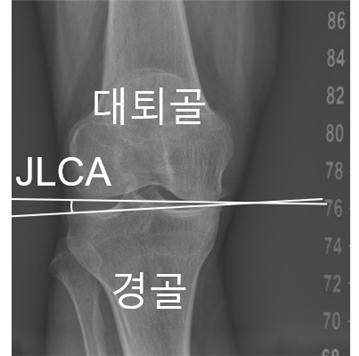

[ÀÇÇнŹ®¡¤Àϰ£º¸»ç=±èÇö±â ±âÀÚ] ¹«¸­ °üÀýÀ» ÀÌ·ç´Â »À°¡ ¹ú¾îÁø Á¤µµÀÎ '°üÀý¼± ¼ö·Å°¢(JLCA)'ÀÌ ³ëÀεéÀÇ ´ëÇ¥ÀûÀÎ ¸¸¼º ÁúȯÀÎ ÅðÇ༺ °üÀý¿°¿¡ ¿µÇâÀ» ¹ÌÄ¡´Â °áÁ¤ÀûÀÎ ÁöÇ¥¶ó´Â ¿¬±¸°á°ú°¡ ³ª¿Í ÁÖ¸ñµÈ´Ù.

¹«¸­ °üÀý¼± ¼ö·Å°¢(»çÁøÁ¦°ø=¼­¿ï´ëº´¿ø)

¿¬±¸ÆÀÀº ÀΰøÁö´É ±â¹Ý ¼ÒÇÁÆ®¿þ¾î¸¦ Ȱ¿ëÇØ ȯÀÚÀÇ ÇÏÁö ¿¢½º·¹ÀÌ »çÁøÀ» ºÐ¼®Çß´Ù. À̸¦ ÅëÇØ ¾ûµ¢ÀÌ-¹«¸­-¹ß¸ñ °¢µµ(HKAA), °üÀý¼± ¼ö·Å°¢(JLCA), °üÀý¿° ÁßÁõµµ(K-L µî±Þ) µî ÁÖ¿ä ÁöÇ¥¸¦ ÃøÁ¤Çß´Ù.

¿¬±¸ÆÀÀº ¹«¸­ °üÀýÀ» ÀÌ·ç´Â ´ëÅð°ñ°ú °æ°ñ »çÀÌÀÇ °üÀý¼±ÀÌ ¹ú¾îÁø Á¤µµÀÎ '°üÀý¼± ¼ö·Å°¢(JLCA)'ÀÌ ÀÌ·¯ÇÑ °¡¼Ó ÁøÇàÀ» ¿¹ÃøÇÏ´Â °øÅë ÁöÇ¥ÀÓÀ» ¹àÇô³½ °Í.

¿ì¼± Ãʱ⿡ ÃøÁ¤µÈ JLCA°¡ 1¡Æ Ä¿Áú ¶§¸¶´Ù OÀÚÇü ȯÀÚ¿¡¼­ 12.9%, XÀÚÇü ȯÀÚ¿¡¼­ 19.4%¾¿ °¡¼Ó ÁøÇà À§ÇèÀÌ Áõ°¡Çß´Ù. ƯÈ÷ OÀÚÇü ȯÀÚÀÇ °æ¿ì °üÀý¿° ÁßÁõµµ°¡ ³ôÀ»¼ö·Ï °¡¼Ó ÁøÇà À§ÇèÀÌ Áõ°¡ÇßÀ¸¸ç, Áߵ ÀÌ»ó(Grade III, IV) ´Ü°è¿¡¼­´Â Á¤»ó±º(Grade 0) ´ëºñ ¾à 4~5¹è ³ô¾Ò´Ù.